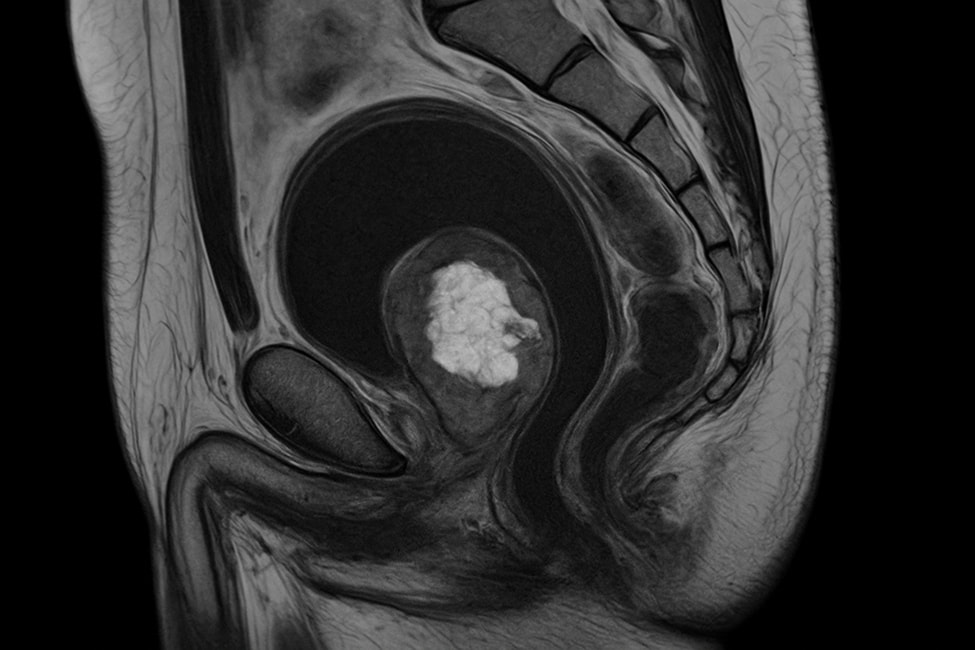

МРТ прямой кишки — это высокоточный метод визуализации, применяемый для оценки состояния слизистой, стенок и окружающих тканей аноректальной области. Он основан на принципе магнитного резонанса: сильное магнитное поле и радиоволны создают послойные изображения, позволяющие детально рассмотреть даже мельчайшие структуры без хирургического вмешательства.

Магнитно-резонансная томография прямой кишки помогает выявить воспаления, рубцовые изменения, свищи, полипы и опухоли. Она особенно информативна для диагностики злокачественных образований, оценки распространения опухоли на соседние органы и подготовки к хирургическому вмешательству.

Методика дает возможность визуализировать стенку кишки послойно, определить глубину поражения, состояние сфинктерного аппарата, лимфатических узлов и сосудов. Ректальное МРТ часто используется как дополнительный инструмент, когда данные эндоскопии или УЗИ недостаточны.

При необходимости обследование проводится с контрастным усилением. Контрастное вещество помогает уточнить границы патологического очага и выявить скрытые сосудистые изменения. Благодаря этому МРТ прямой кишки используется как «золотой стандарт» при оценке аноректальных структур.

Современные аппараты обладают высокой точностью и позволяют получать снимки в трех проекциях. Благодаря этому магнитно-резонансная томография заднего прохода дает возможность обнаружить минимальные патологические изменения, которые невозможно увидеть при традиционных методах.

Высокая точность метода позволяет выявить патологию на ранней стадии, что значительно повышает шансы на полное выздоровление. При онкологических процессах именно ректальное МРТ помогает уточнить стадию опухоли и определить объем операции.